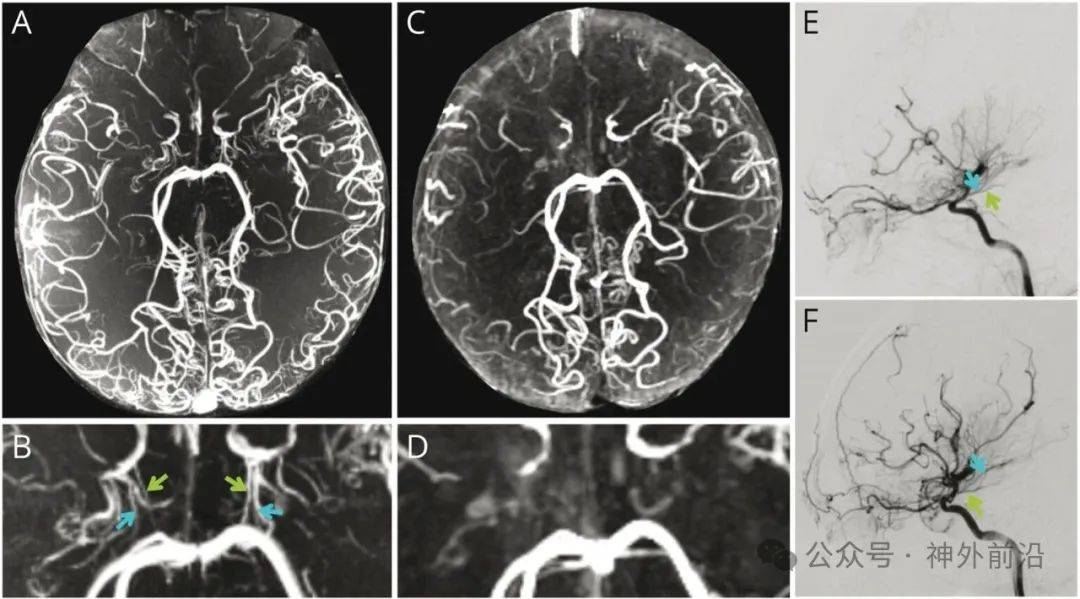

9、2025年4月,北京天坛医院赵继宗院士团队成功为86岁患者切除65cm巨大脑膜瘤,刷新高龄神经外科手术纪录,为同类病例治疗提供天坛医院核磁加急了重要参考图1 赵继宗院士为患者做手术一手术背景与患者情况肿瘤特征患者秦女士的脑膜瘤直径达65cm,约占大脑四分之一体积,核磁影像显示其白色阴影几乎占据颅内四分之一空间。